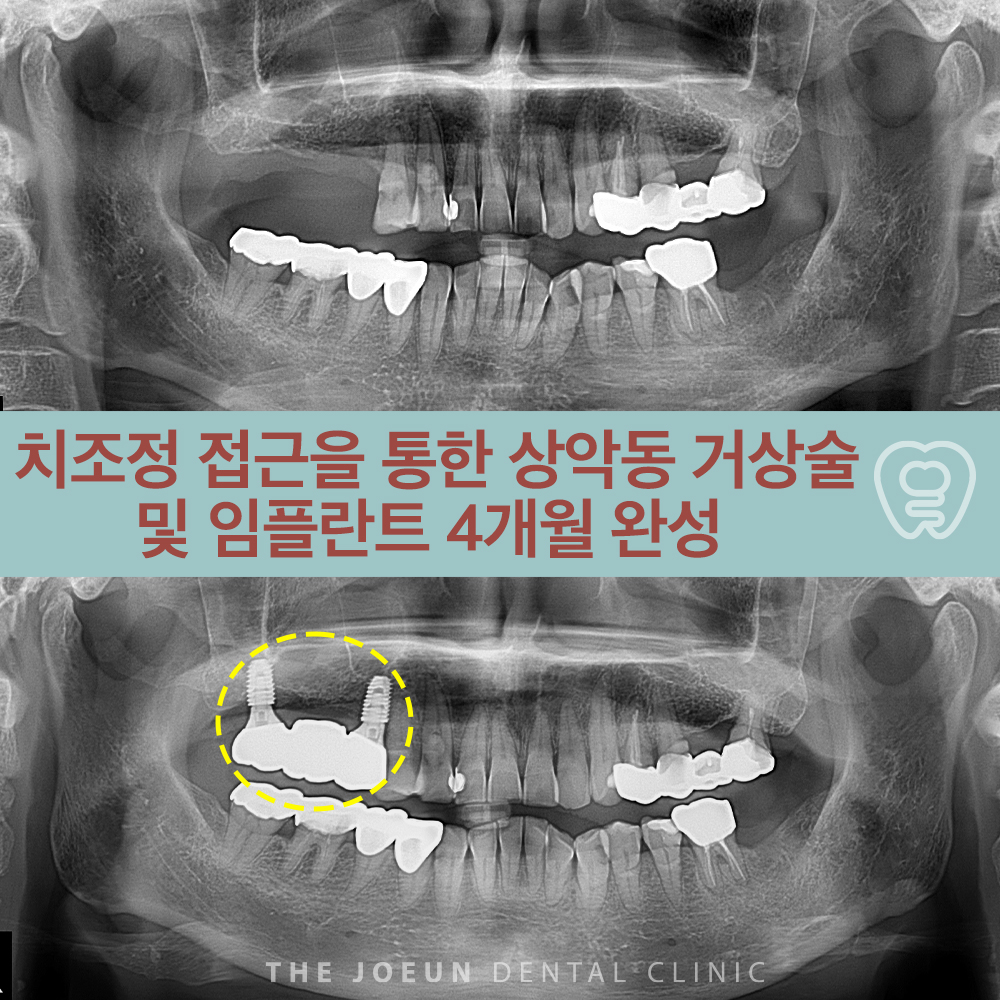

다사치과 치조정 접근을 통한 상악동 거상술 및 임플란트 4개월 완성

다사치과 치조정 접근을 통한 상악동 거상술 및 임플란트 4개월 완성 임플란트는 치과 치료에서 가장 널리…